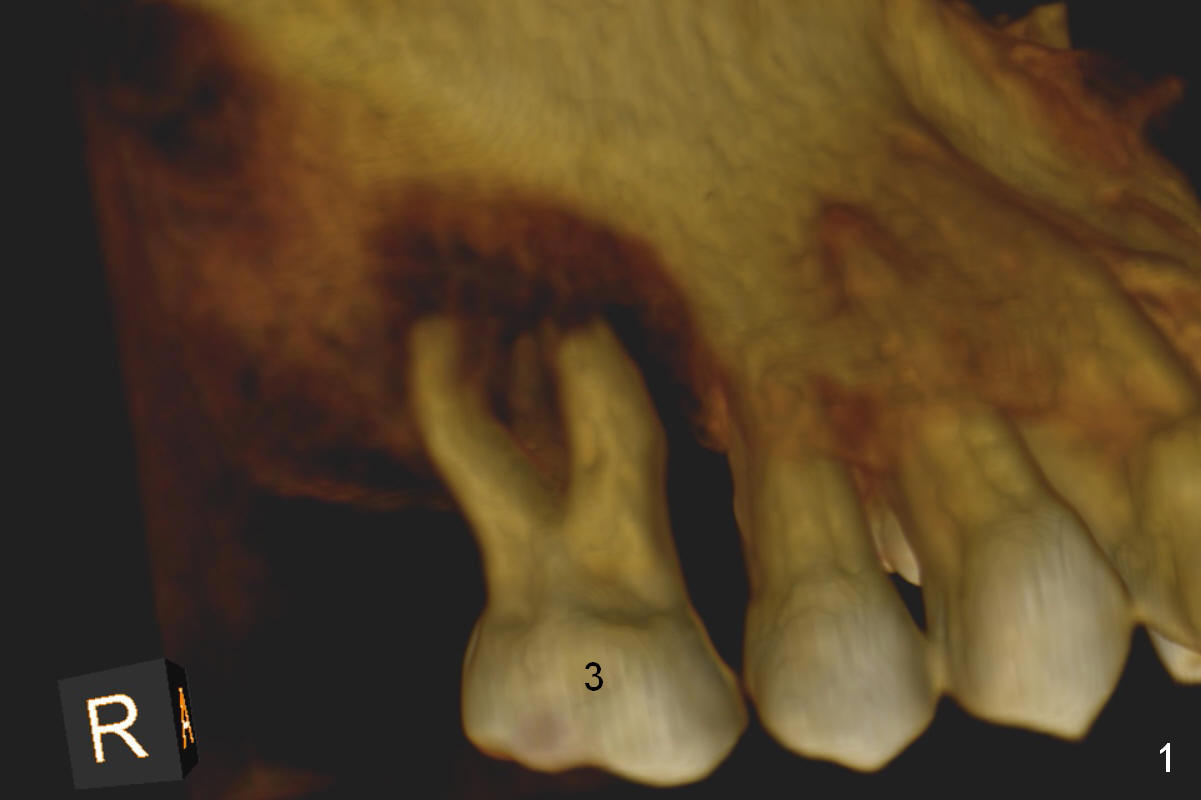

It may take 6 months for #19 implant re-placement after socket preservation. The tooth #3 is symptomatic (Fig.1). In spite of implant failure at #19, the best treatment for #3 of the same patient is still immediate implant. Previous practice is to place an implant as long as possible (Fig.2). The coronal threads are not covered by the native bone. Bone graft (red circles) cannot guarantee thread coverage. Periimplantitis may develop more likely in periodontitis patients if bone graft is not tightly packed.